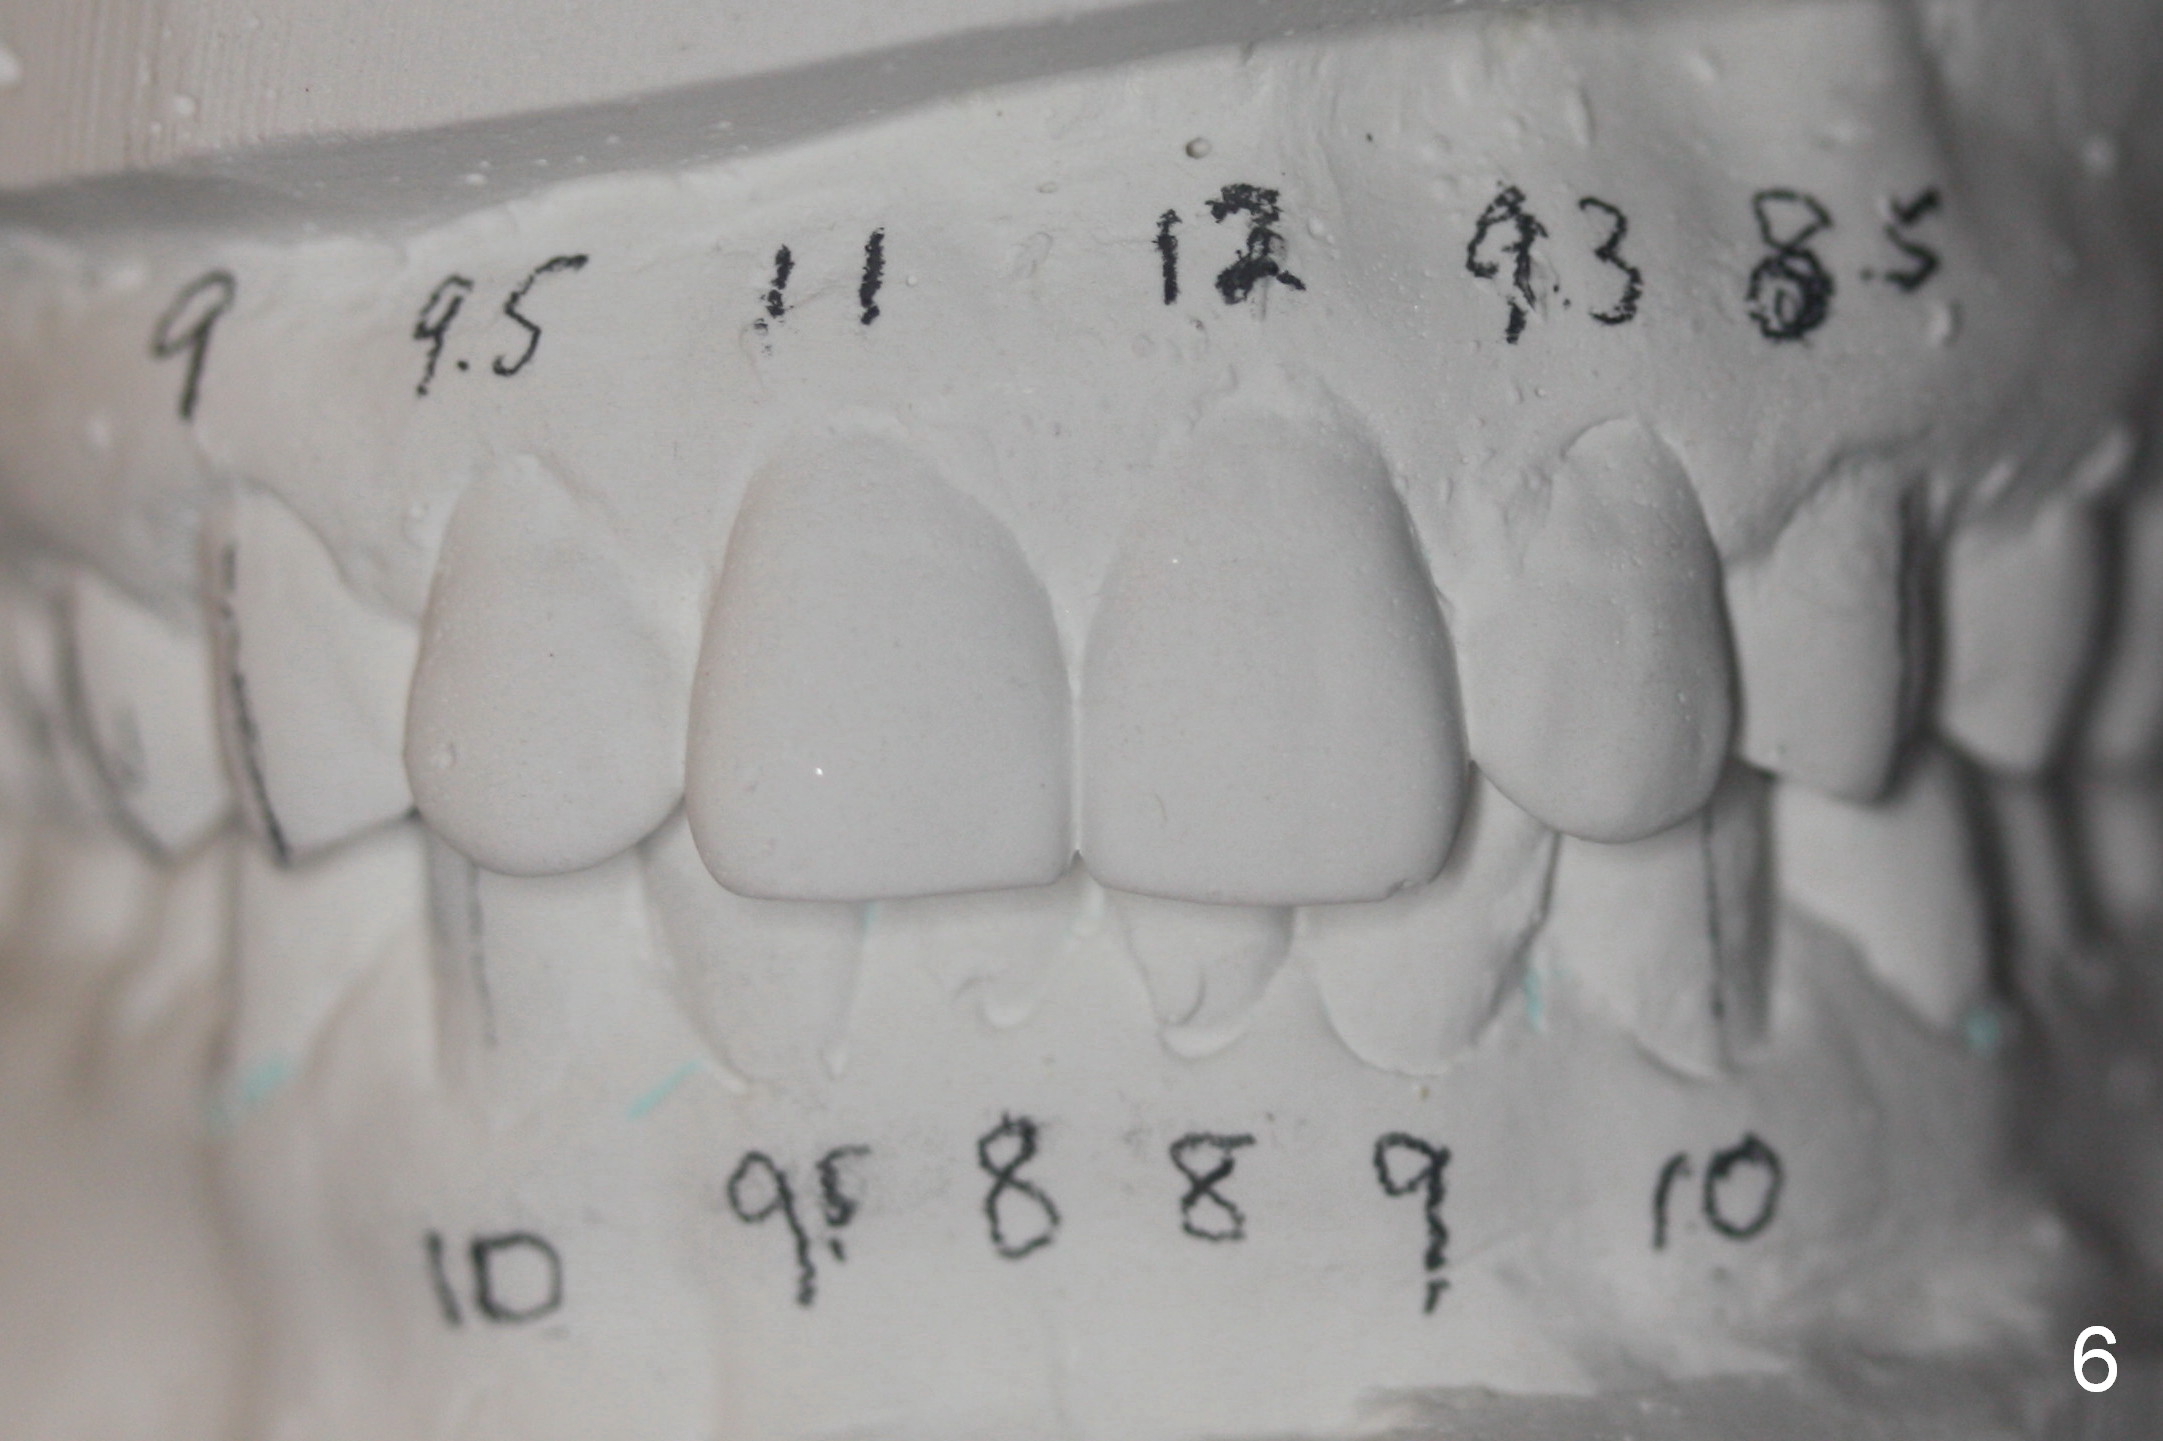

A 42-year-old man requests orthodontic treatment after extraction of the teeth #1, 16, 17, and 32, because it is easier for him to maintain oral hygiene post extraction. He thinks that orthodontic treatment will do the same. He appears to care about his dental alignment: not showing his teeth while smiling (Fig.2). The facial profile is within normal limit (Fig.3). His lower anterior teeth are moderately crowded (Fig.4) with anterior deep overbite and overjet (Fig.5,6). The deep overbite is more appreciated when the model is viewed posteriorly (Fig.7), approximately 90% of the upper incisors are covered by the lower anterior ones. More lingual surfaces are shown in another case before (Fig.8) and after (Fig.9) orthodontic treatment. With differential placement of brackets on the canines vs. incisors (Fig.6), the deep bite should be able to be corrected. Proximal reduction may be necessary.